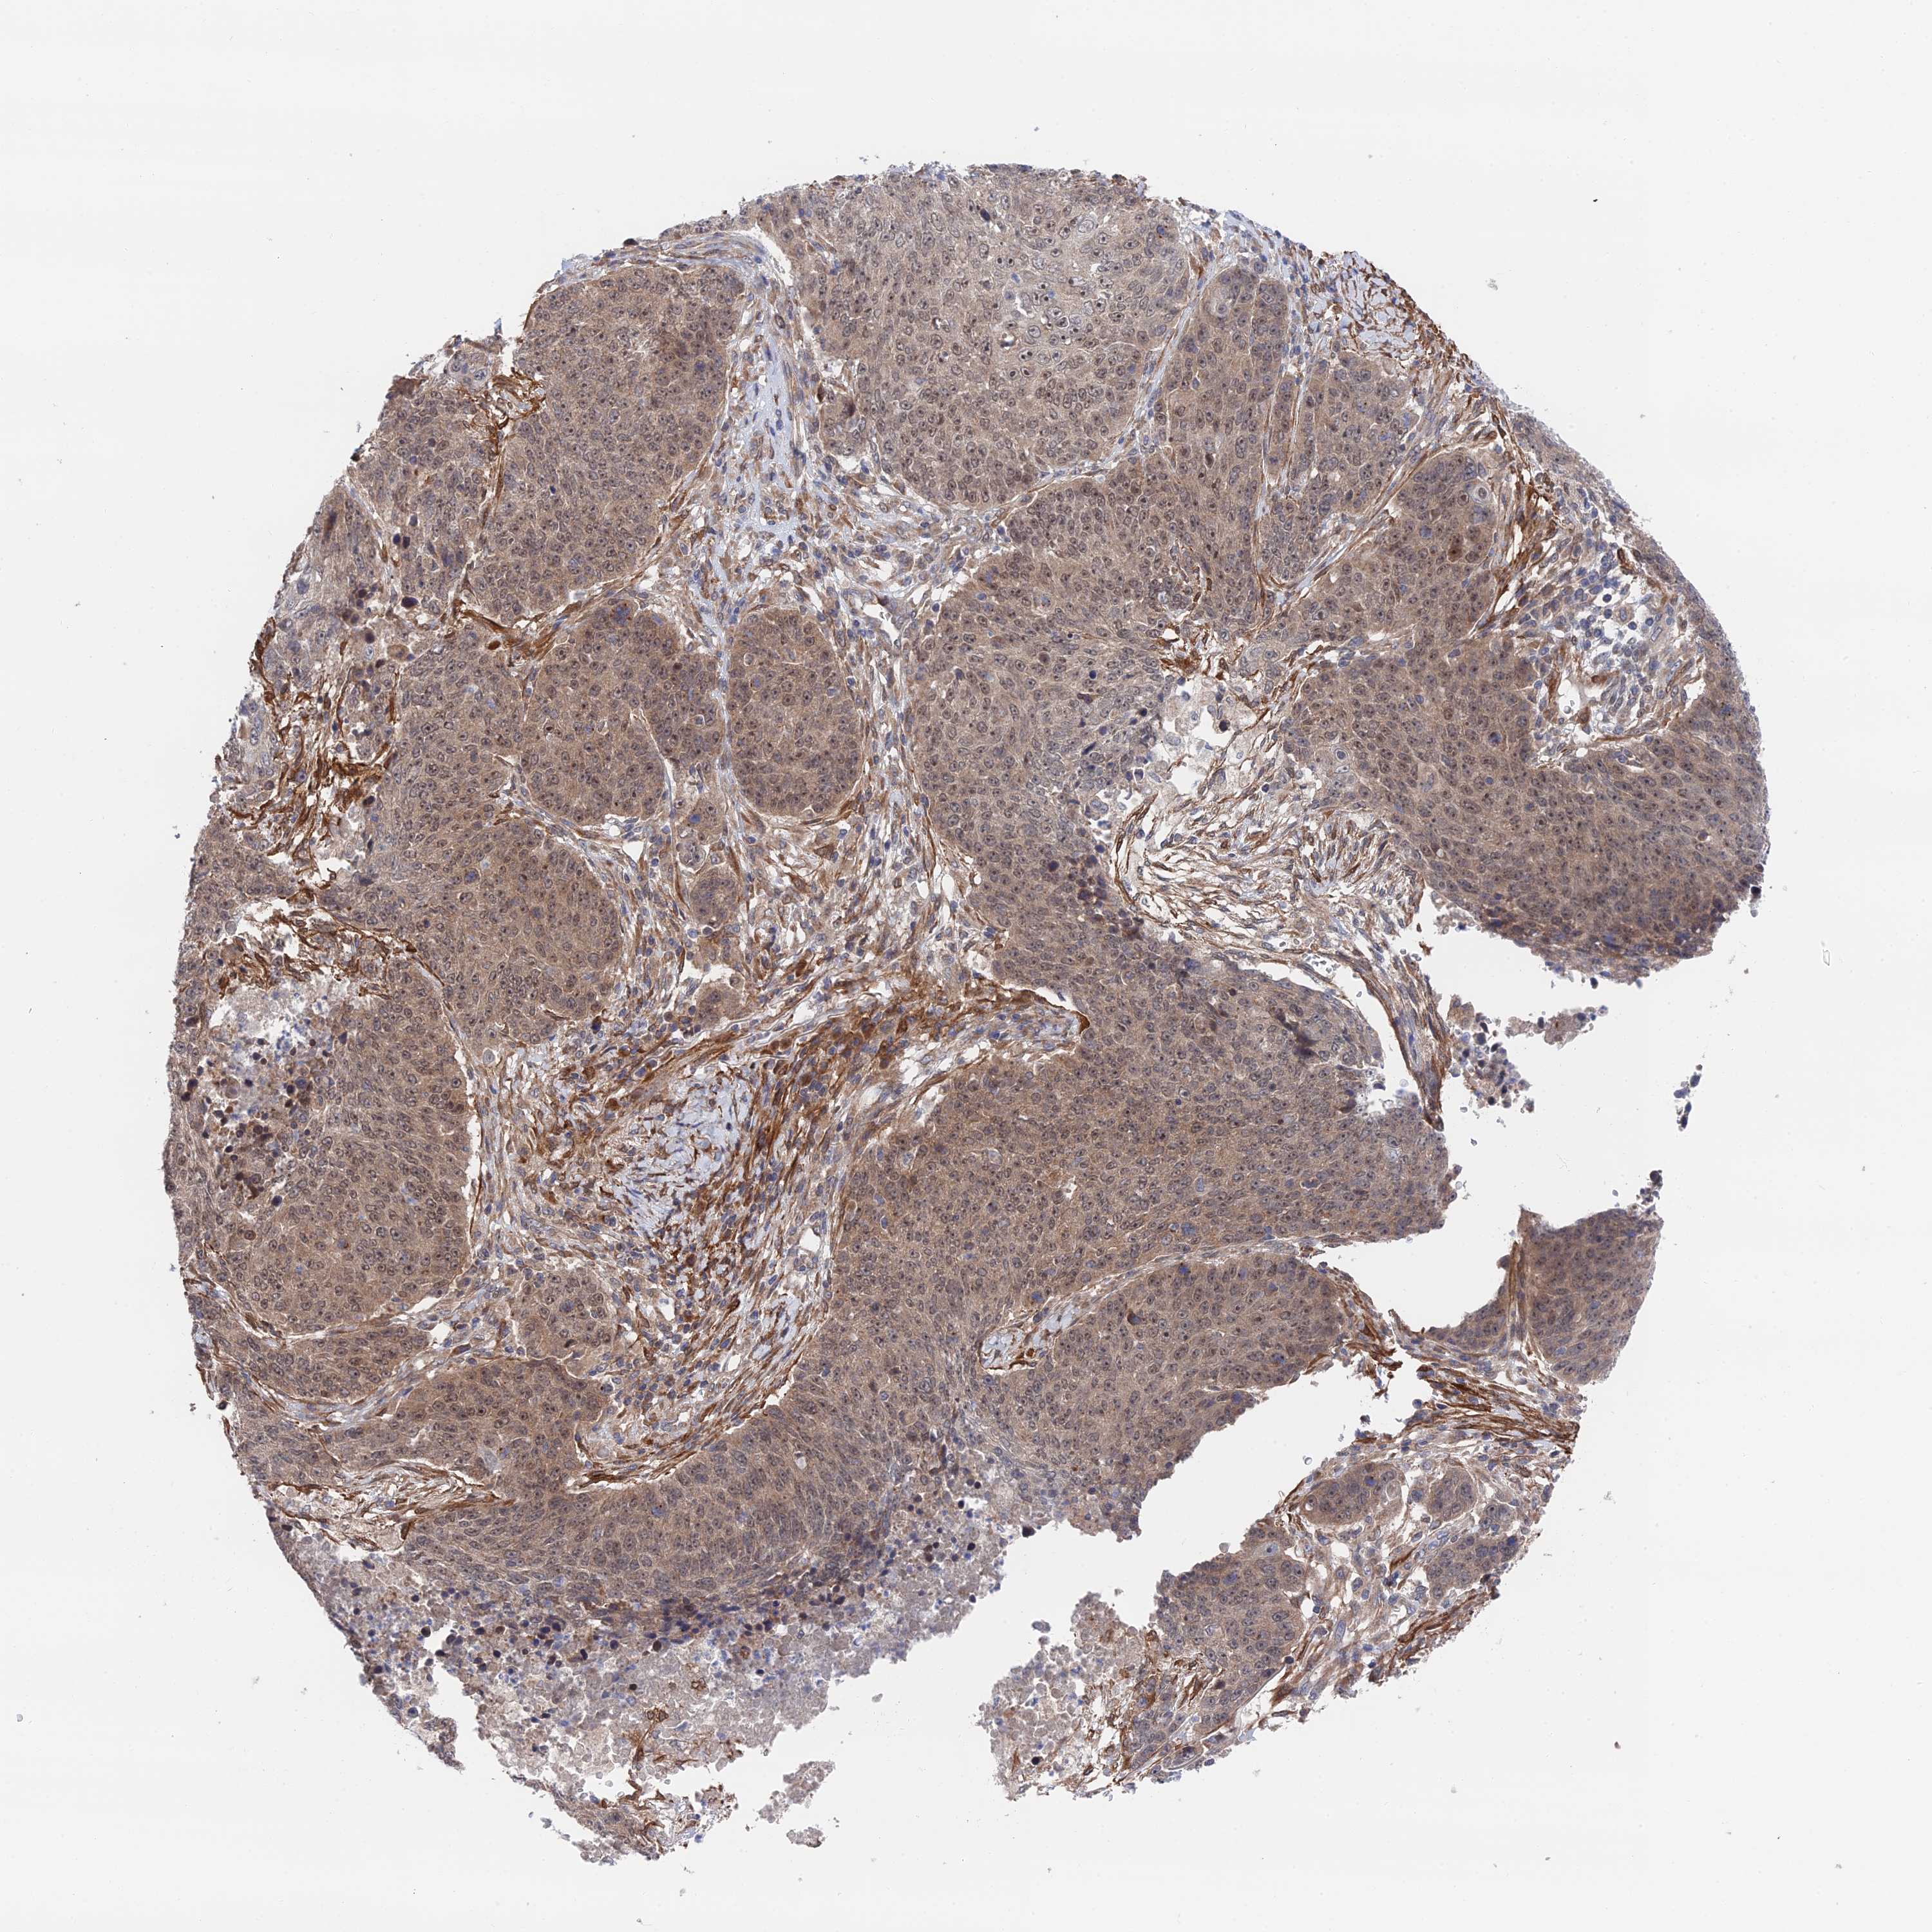

LUNG ADENOCARCINOMA (VALIDATION) - Interactive survival scatter ploti

The Survival Scatter plot shows the clinical status (i.e. dead or alive) for all individuals in the patient cohort, based on the same data that underlies the corresponding Kaplan-Meier plots. Patients that are alive at last time for follow-up are shown in blue and patients who have died during the study are shown in red.

The x-axis shows the expression levels (FPKM) of the investigated gene in the tumor tissue at the time of diagnosis. The y-axis shows the follow-up time after diagnosis (years). Both axes are complimented with kernel density curves demonstrating the data density over the axes. The top density plot shows the expression levels (FPKM) distribution among dead (red) and alive patients (blue). The right density plot shows the data density of the survived years of dead patients with high and low expression levels respectively, stratified using the cutoff indicated by the vertical dashed line through the Survival Scatter plot. This cutoff is automatically defined based on the FPKM cutoff that minimizes the p-score. The cutoff can be changed by dragging the vertical line or by entering a cutoff value in the square labeled "Current cut-off".

Under the Survival Scatter plot the p-score landscape (black curve; left axis) is shown together with dead median separation (red curve; right axis). Dead median separation is the difference in median mRNA expression between patients who have died with high and low expression, respectively. It is calculated as follows: median FPKM expression of dead patients with high expression - median FPKM expression of dead patients with low expression. This is intended to aid the user in visually exploring custom cutoffs and the associated p-scores and dead median separation.

Individual patient data is displayed and can be filtered by clicking on one or more of the category buttons on the top of the page. Categories describing expression level and patient information include: high, low, alive, dead, female, male and tumor stages. The scale of the x-axis can be toggled between linear and log-scale by clicking on the "x log" button. Mouse-over function shows TCGA ID, patient information and mRNA expression (FPKM) for each patient.

& Survival analysisi

Kaplan-Meier plots summarize results from analysis of correlation between mRNA expression level and patient survival. Patients were divided based on level of expression into one of the two groups "low" (under cut off) or "high" (over cut off). X-axis shows time for survival (years) and y-axis shows the probability of survival, where 1.0 corresponds to 100 percent.

ZNF320 is not prognostic in Lung Adenocarcinoma (validation)

: 17.13

P scorei

N/A

Average pTPM 14.9

Number of samples 105